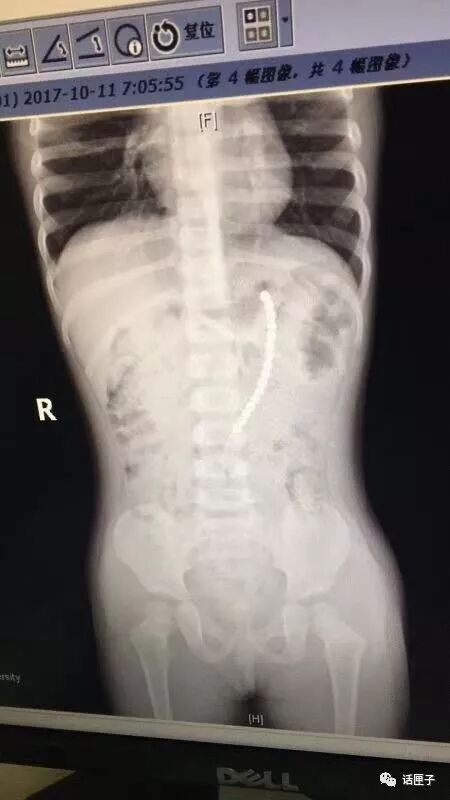

医生给这个小女孩拍了片子。没想到,在小女孩肚子里一共有19颗珠子

医生给孩子做了胃镜,取出了胃里的六颗巴克球。不幸的是,还有一排珠子已经穿出胃壁,到小女孩的肚子里去了

医生在腹腔镜下发现,剩余的珠子一颗连一颗构成一串,一端在胃里,另一端在小肠里。孩子的肠子和胃里面,都被巴克球穿孔了。医生只好取出珠子后,再把小女孩的胃和小肠补上。万幸的是,由于送医及时,小女孩已经脱离了危险。